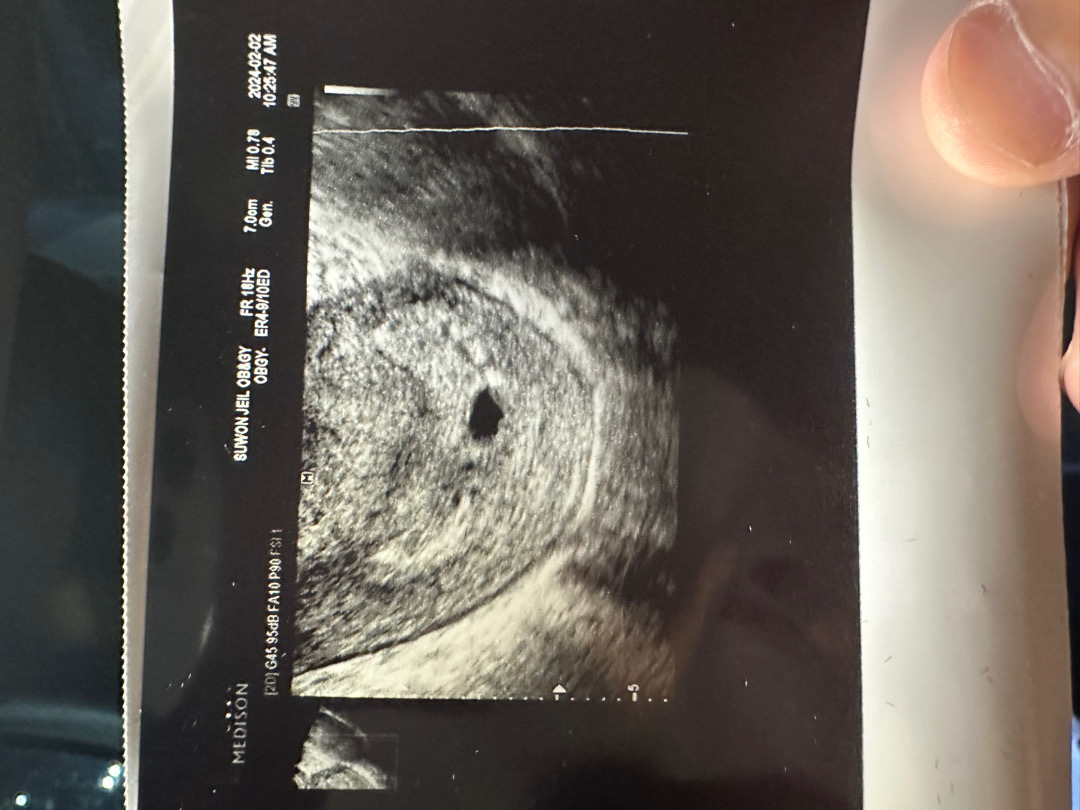

아기집 초음파사진 괜찮은걸까요?

5주2일차 아기집 사진봤는데 경계선도 흐릿하고 난황도 보이질 않아요 ㅠㅠ 크기도 모르겠고.. 의사쌤은 괜찮다고 했는데 어때보이시나요?.?